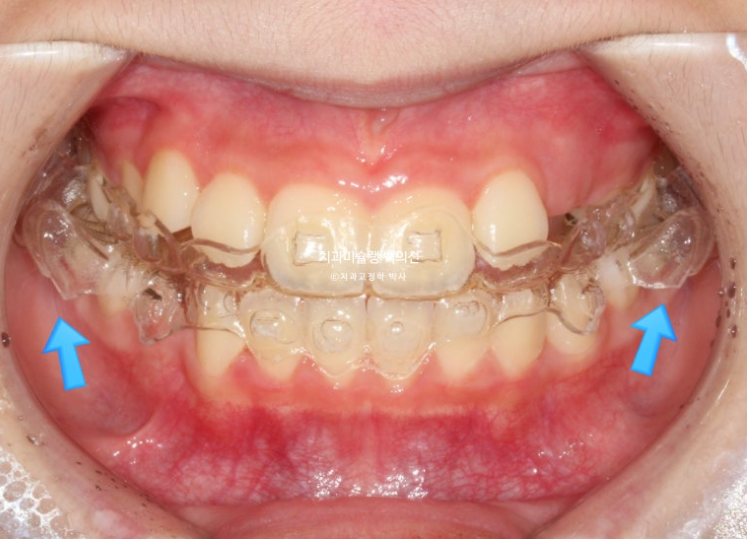

24.12

파란화살표 부분을 보자면

장치 양옆에 날개처럼 튀어나온 부분이 Wing 이며 이 부분이 아래턱의 위치를 정상위로 유도합니다.

23.11

사진의 파란화살표처럼 위 아래 윙 끼리 엇갈려 물리며 아래턱을 전방위치 시키며, 최대성장기와 맞물리면 하악골 성장까지 유도하게 됩니다.